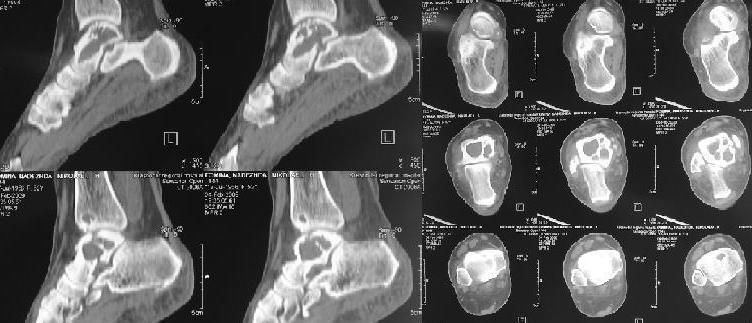

Киста таранной кости

Здраствуйте коллеги! К нам обратилась пациентка 52 лет с болями в области голеностопного сусатва.

Со слов болеет в течение 5 лет. По м\ж лечилась консервативно. Выполнили Rg- и KT- . Выявлена киста таранной и большеберцовой костей. Взята открытая биопсия таранной кости(результат пока не готов). Визуально в тараной кости полость, без какого либо содержимого.

Какую тактику лечения вы посоветуете? Выполнить костную аутопластику (с сомнительным результатом) или же сразу выполнить астрогалэктомию? Или же другие варианты?

Plz pay attention that not whole the talus is hollow.